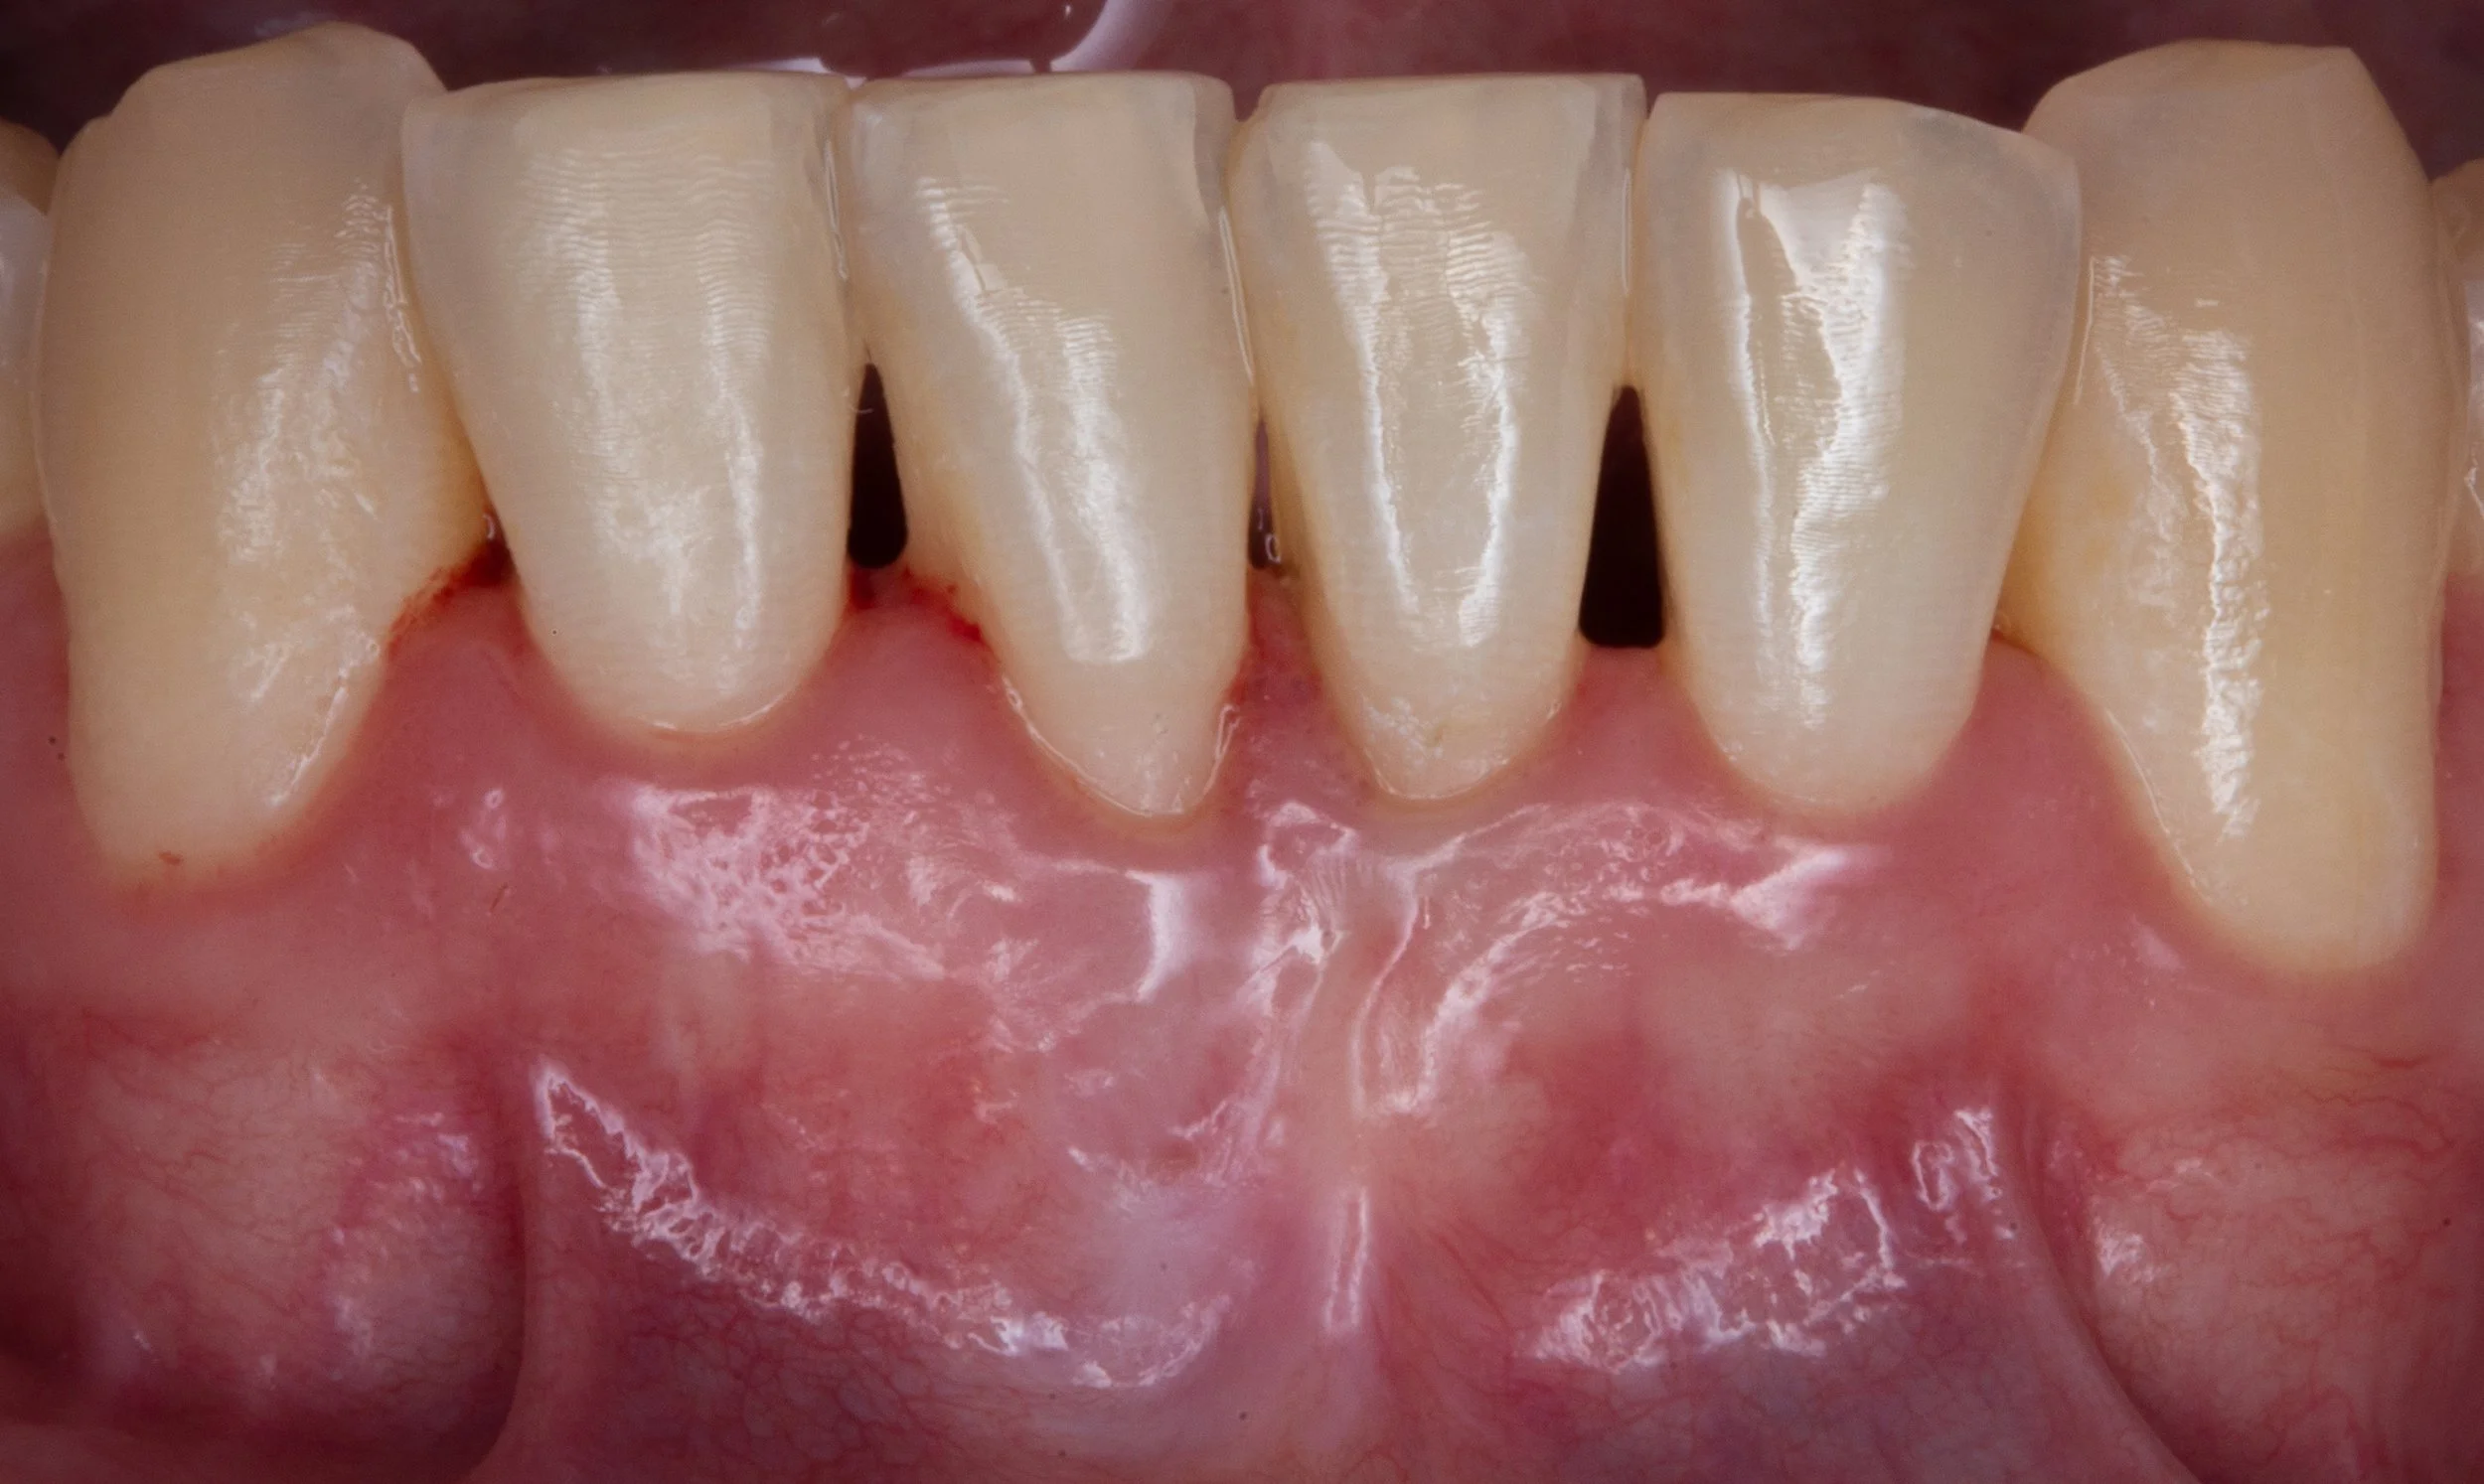

Gum recession is a common dental condition that you may have been referred to a periodontist to evaluate. If you have gum recession, the pink gum tissue surrounding teeth has pulled away from your tooth, exposing more of the tooth or its root. As shown in the before and after pictures on this page, gum recession can occur anywhere in your mouth, and may require surgical intervention. Gum recession can occur due to several reasons, including: